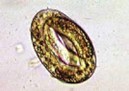

The McMaster technique is a simple quantitative faecal egg count test used to estimate eggs per gram (represented as e.p.g) in a known volume of faecal suspension to the nearest 50 e.p.g. X2 0.15ml of solution is placed into the counting chambers and the sample is examined under a microscope. Systematically, eggs lying within the chambers are counted and an e.p.g result calculated using the following formula;

EPG = total eggs counted in both chambers x50.

This quick method allows us to accurately monitor strongyle type eggs, Nematodirus, tapeworm (to an extent) and coccidia burdens. Some species like Lungworm, encysted tapeworm and Liver Fluke require additional testing and should not use the McMaster technique as a sole means of determining status. To minimise the chance of missing potential eggs, always used a fresh faecal sample, ideally less than 24 hours old. If samples are being pooled, bring in samples from individual animals (with clearly labelled ID). The lab will pool the samples. Refrigerate the sample if there is going to be a delay in getting it to the lab. It is important to point out that if no eggs are seen, it does not guarantee an animal or mob are parasite free, it just means that no eggs were detected in that particular sample. If a result comes back low or negative but an animal is still presenting with symptoms, consult your veterinarian.

StronStrgyles